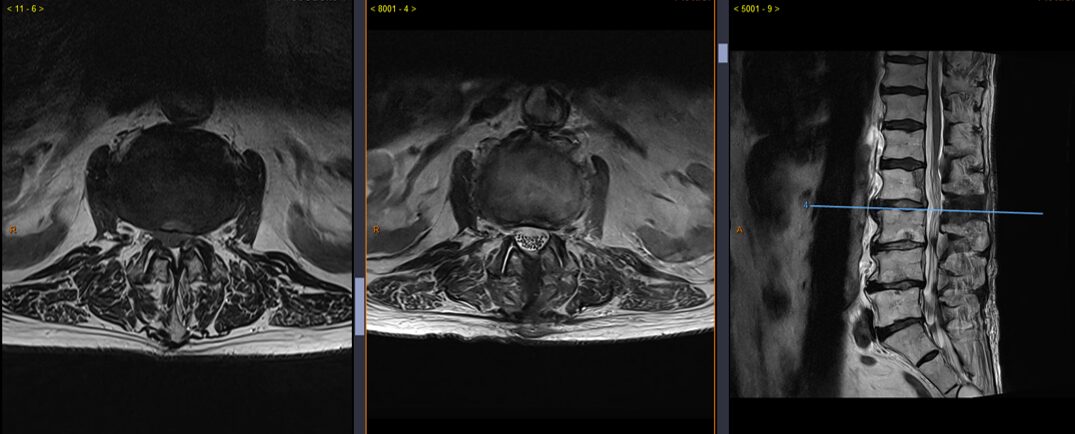

Sténose du canal lombaire L2-L3 avant et après chirurgie de décompression.